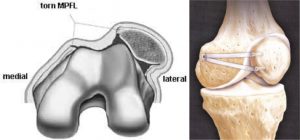

Apex patellae

Apex patellae 117 фото